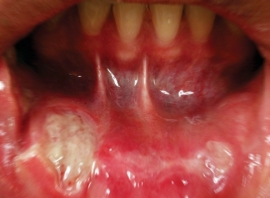

베체트병 치료제 아프레밀라스트(Apremilast)의 치료효과가 구강궤양에서 만큼은 뚜렷하게 나타났다.

베체트병은 반복적인 구강궤양을 비롯해 음부궤양, 피부궤양 등 전신적인 자각면연반응을 특징으로 한다. 그동안 해당 질환에서 기존 치료제들의 효과가 좋지 못했기 때문에 새로운 치료제들에 대한 수요가 높았던 상황. 연구팀은 경구용 포스포디에스테라아제(PDE)-4 억제제로 다양한 염증경로를 조절하는 아프레밀라스트의 치료 효과를 평가했다.

결과에 따르면 아프레밀라스트의 구강궤양 치료효과는 분명했다. 치료 12주차 구강궤양의 평균 발생치는 아프레밀라스트 투약군이 위약군보다 유의하게 낮았다(아프레밀라스트군 0.5±1.0 vs. 위약군 2.1±2.6, P < 0.001). 또 동일시점에서 아프레밀라스트 투약군이 위약군보다 구강궤양의 통증경감 정도가 더 컸다(아프레밀라스트군 -44.7±위약군 24.3 mm vs. -16.0±32.5 mm, P < 0.001).